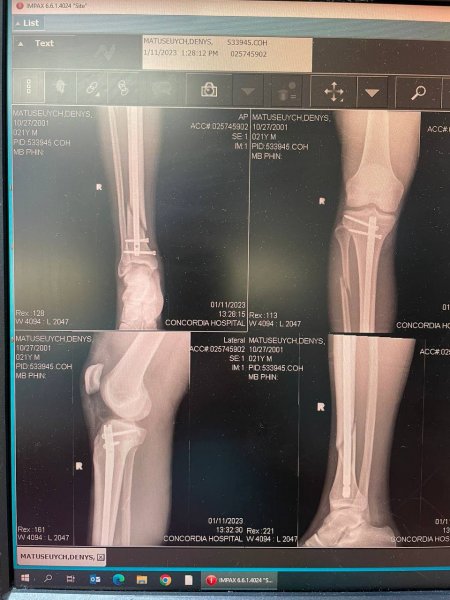

Мені зробили операцію. Вставили 4 болти: два під коліном та два над гомілкостопом й спиця по середині кістки. Повне відновлення до року, а на сам лід можна пробувати виходити коли зросте кістка — 3-4,5 місяці, — розповів Денис про те, як отримав травму.